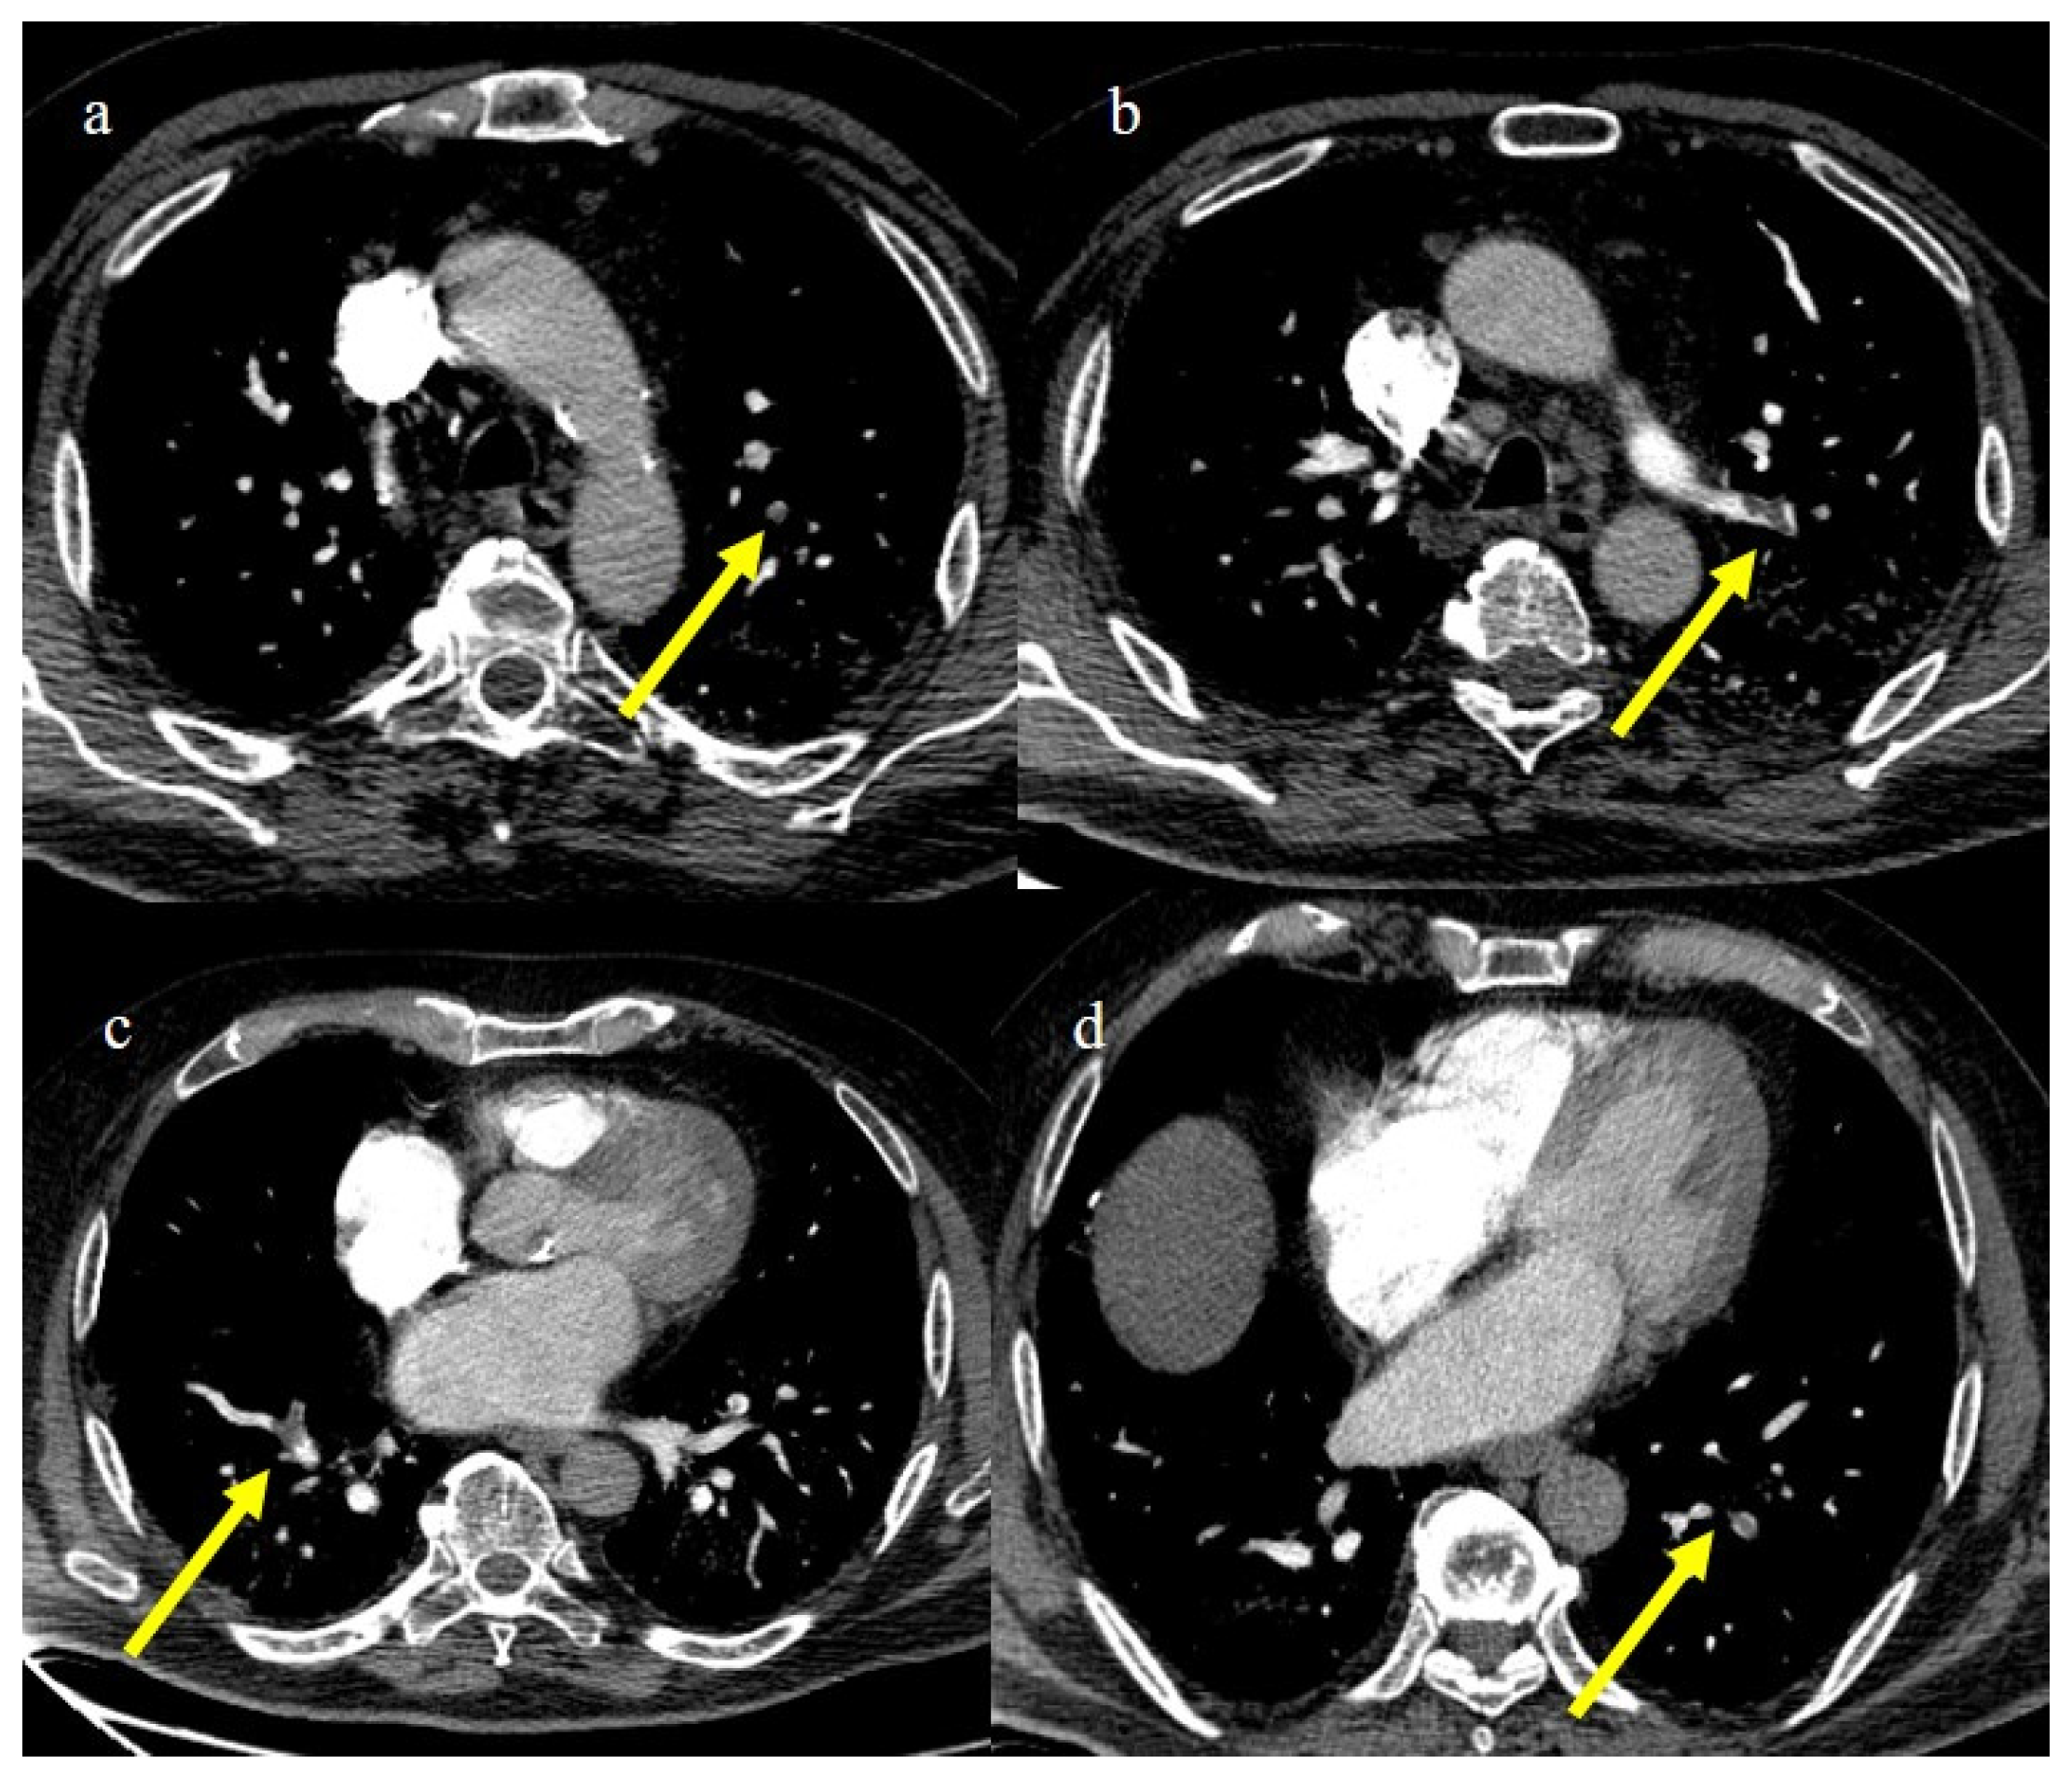

Figure 22.

Chest CT of an 81-year-old patient in ICU during the transition period of Delta-Omicron variant (January 2022) (vaccination status unknown, probably concerns a breakthrough infection) with severe COVID-19 pneumonia with CT-SS of 23/25 with diffuse interstitial thickness and consolidations in the superior lobes, as visualized in image (a). The CT pulmonary angiogram showed thrombosis in the distal portion of the left pulmonary artery (yellow arrow) in image (b); severe pneumonia with consolidations in the apical segment of inferior lobes in image (c) and thrombosis in a segmentary branch (yellow arrow) in image (d).